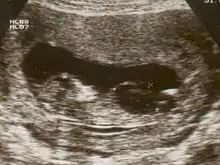

Ultrasound scan of a fetus with megacystis

Fetal megacystis is diagnosed during pregnancy by ultrasound imaging procedures. Since it can be associated with genetic abnormalities, further ultrasounds and tests may be administered during pregnancy. It may also be diagnosed as megalocystis, and/or termed megabladder, which is the same condition.